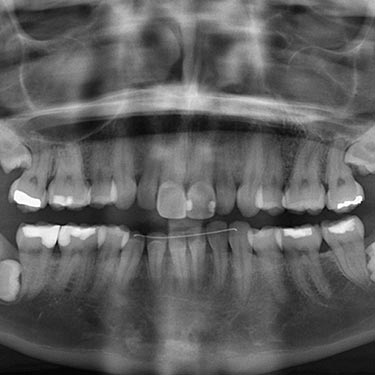

Above all, we must consider the reasons for taking them. X-rays are an indispensable tool to diagnose problems that cannot be seen with the naked eye. In particular, they are important for identifying caries between teeth or under old fillings, the position of impacted wisdom teeth, the bone level between teeth, lesions or infections affecting the bone … That’s why dental examination cannot be considered complete without radiographs.